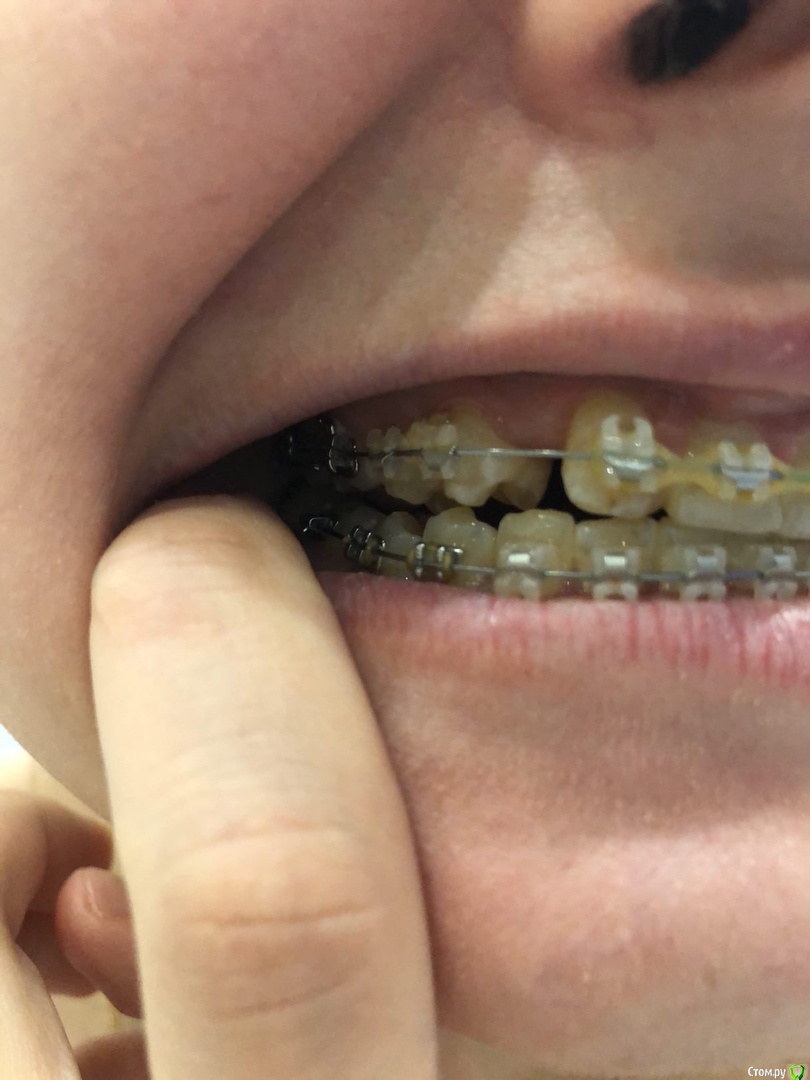

Когда в юности зубы начали меняться, то оказалось что на верхней челюсти отсутствуют резцы, нет зачатков (хотя молочные были).

Врач сказал что это адентия и предложила поставить брекеты.

В 15 Относила брекеты,  раздвинули место под резцы и сделали зубы на стекловолокне мостики, ждали пока буду повзрослей чтобы поставить импланты.

В 20 лет пришла к хирургу что б поставить импланты, он сказал что корни клыков стоят домиком и места под имплант нет, отправил опять к ортодонту.

За 5 лет корни уехали.

Теперь уже другой врач ставит мне опять брекеты и собирает все зубы вместе.

Главная проблема на сегодняшний день в том, что щелкает сустав  (с левой стороны), а челюсть начала уезжать в право.

Иногда чувствуется небольшое онемение лица слева

Врач говорит что все пройдет когда зубы все соберутся, но я не понимаю как, ведь верх меньше на два зуба и нет вообще смыкания контакты нарушены,

да и зубы начали стирать.

Подскажите пожалуйста что делать и к кому обращаться. Сейчас мне почти 27 лет.